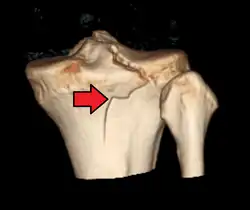

A severe tibial plateau fracture with an associated fibular head fracture

In all injuries to the tibial plateau radiographs (commonly called x-rays) are imperative. Computed tomography scans are not always necessary but are sometimes critical for evaluating degree of fracture and determining a treatment plan that would not be possible with plain radiographs.[6] Magnetic Resonance images are the diagnositic modality of choice when meniscal, ligamentous and soft tissue injuries are suspected.[7][8] CT angiography should be considered if there is alteration of the distal pulses or concern about arterial injury.